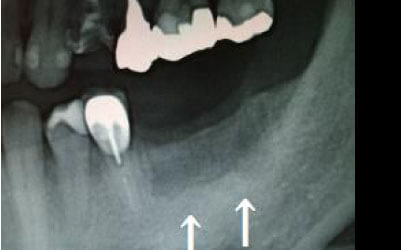

しばらくすると、抜けたままでも慣れてしまうことがありますが、その後に大きな問題が生じることがあります。

1 周囲の歯が早く抜ける

抜けた歯にかかるはずだった噛む力が、知らず知らずのうちに他の歯に負担をかけてしまいます。その結果、残っている歯が突然折れてしまい、抜歯が必要になることがよくあります。

2 歯が傾いてくる、落ちてくる

歯は互いに支え合い、バランスを保っています。そのため、歯が抜けると支えがなくなり、抜けた部分の両隣の歯が傾いたり、上の歯が下に移動してきたりすることがあります。